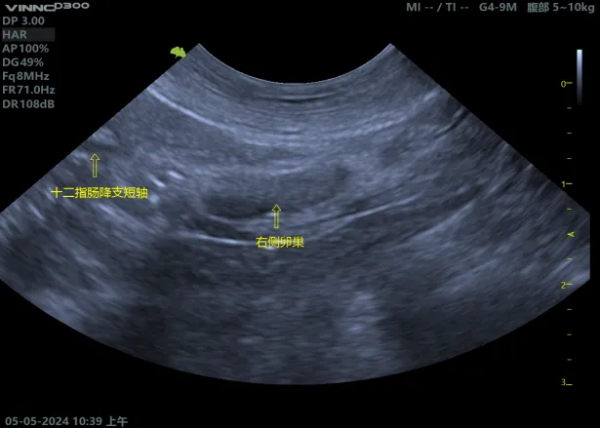

04【超声下表现】 (1)正常子宫影像 (2)子宫残端积液影像 (图片来源:Mattoon, J. S., Sellon, R. K., & Berry, C. R. (2020). Small animal diagnostic ultrasound (4th ed.). Elsevier Saunders.)

05【诊断】 (1)病史:有绝育手术史,之后出现上述症状。 (2)体格检查:腹部触诊可能摸到腹内的团块。 (3)影像学检查: ① 超声:这是首选的、最具诊断价值的方法。可以清晰地看到膀胱附近有一个充满液体的囊状结构(子宫残端),并能评估其大小、壁的厚度和内容物性质。 ② X光:如果积液量很大,可能在X光下看到一个软组织密度的团块影,但不如B超直观。 (4)血液检查: ① 血常规:如果发生感染/蓄脓,白细胞会显著升高。 ② 激素水平检测:检测血清中的孕激素或抗穆勒氏管激素(AMH)水平,可以确认是否存在有功能的卵巢组织残留(即OSS)。这是诊断OSS的金标准。 ③ 阴道细胞学检查:如果有阴道分泌物,可以检查分泌物中的细胞类型,判断是否存在感染和激素影响。